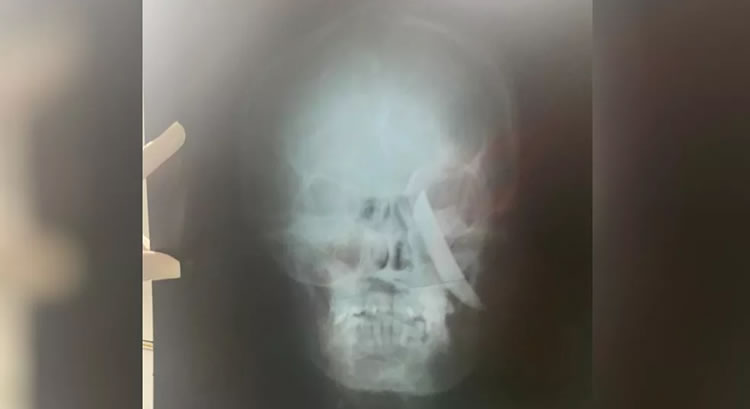

Uma mulher ficou com uma faca cravada no crânio após sofrer uma tentativa de feminicídio nesta segunda-feira (8), em Morada Nova, no interior do Ceará. O suspeito de cometer o crime é o ex-companheiro da vítima. Ele foi preso em flagrante em sua residência após buscas de policiais militares e civis.

A mulher que sofreu a tentativa de feminicídio foi socorrida e encaminhada a uma unidade hospitalar da região, onde recebe cuidados médicos.